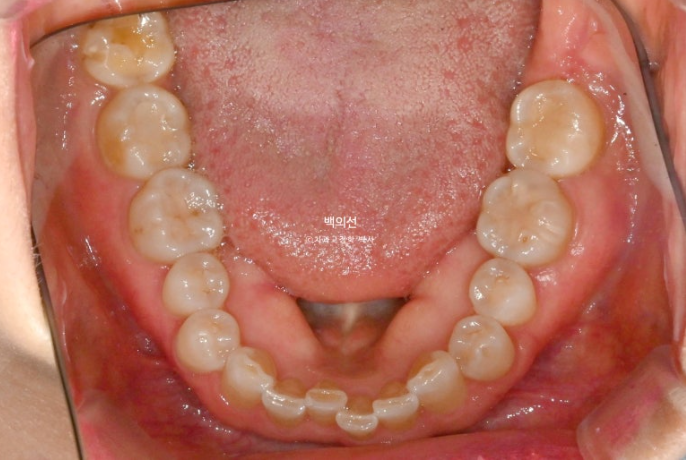

25.02

파란 화살표는 틈을 메워놓은 레진 입니다.

아래 앞니는 누구나 나이가 들면서 점점 틀어집니다.